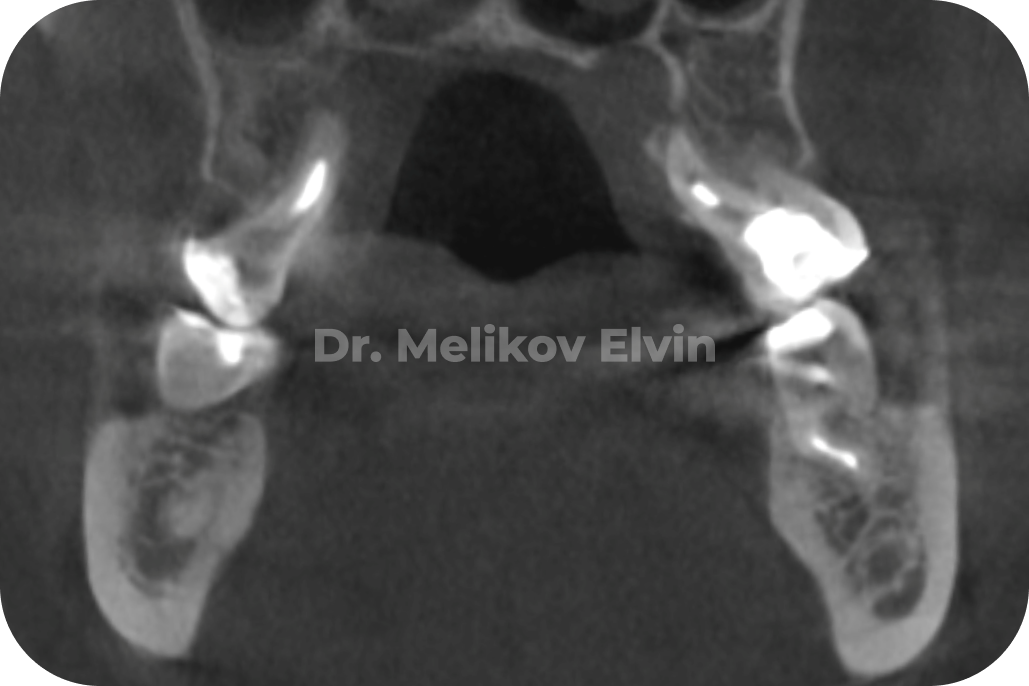

КТ до операции